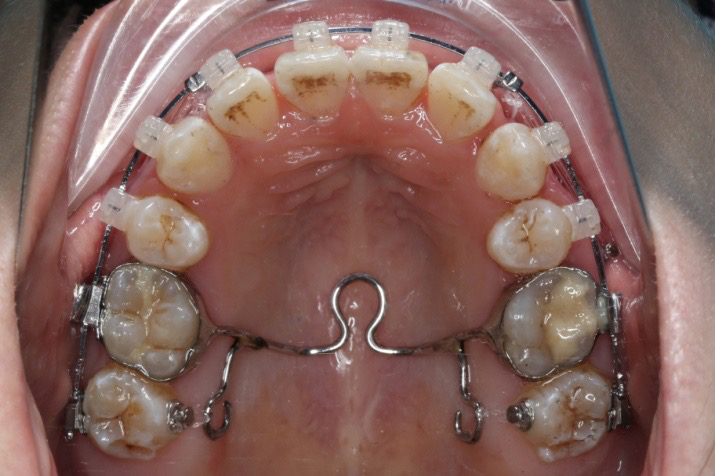

9.第20个月:2018.5.25 ◆ 拆tpa,16/26粘tube上和0.14*25cu-niti 下颌0.018*25niti

10.第22个月:2018.7.23 ◆ 上颌 0.010*25TMA,下颌0.017*25ss43压低曲,双侧后牙垂直牵引

11.第23个月:2018.09.29 ◆ 15/43/16/7/11/21重粘,上0.016*25cu-niti 下0.018niti 上连扎

12.第24.5个月:拆除矫治器,粘接上下舌侧保持器

2018.03.01上TPA加17、27颚侧牵引钩,压低17、27颚尖下颌43、32重粘,下颌0.016*25niti

2018.04.20  间隙基本关闭,上颌重新整平,精调

2018.5.25  (19个月)拆TPA,16、26粘tube 上颌0.14*25cu-niti  下颌0.018*25niti2018.7.23  上颌 0.017*25TMA,下颌0.017*25ss43压低曲,双侧后牙垂直牵引

2018.09.29  15、43、16、17、11、21重粘,上0.016*25cu-niti 下0.018niti 上连扎